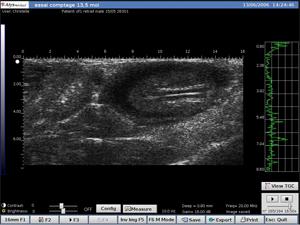

Arterial Vejiga

- Visualización en tiempo real e in vivo de estructuras anatómicas de pequeños animales

- Visualización y medición de la forma y el tamaño de los tumores subcutáneos y ortopédicos

- Visualización del desarrollo embrionario